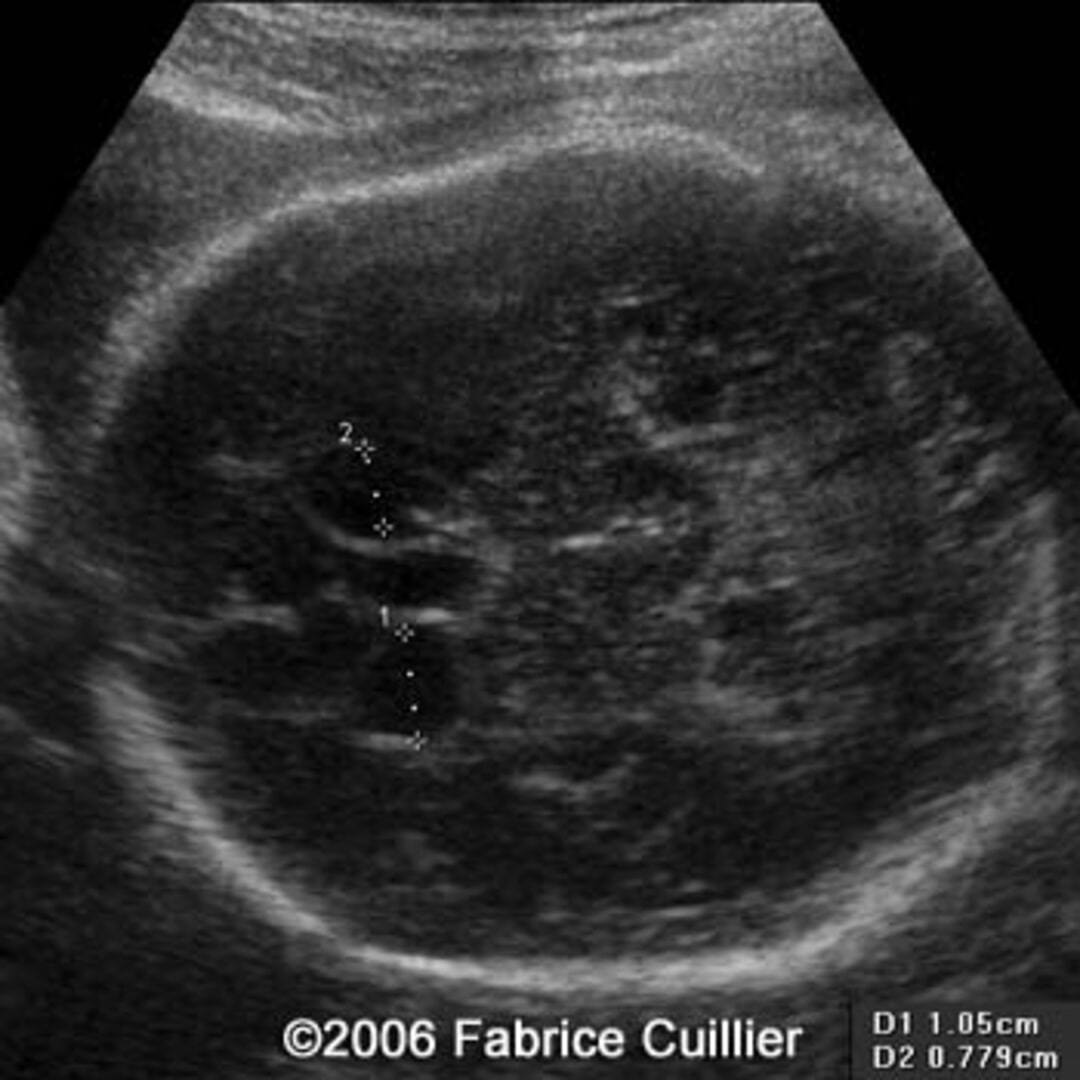

From thefetus.net

📃 Idiopathic subependymal pseudocyst Horn Pseudocyst Definition A pseudocyst is an abnormal collection of tissues and fluids that often develops as a result of leakage from an organ such as the adrenal glands, spleen or. Pseudo horn cysts results from sectioning of a markedly papillomatous skin. True horn cysts represent foci of orthokeratosis within the substance of the lesion, by. So i made a video to explain.. Horn Pseudocyst Definition.